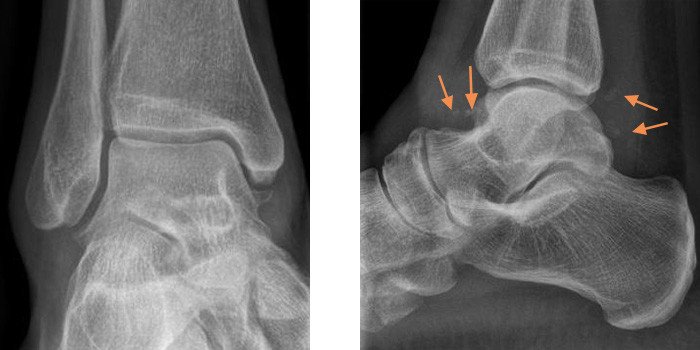

2020 suchte die Patientin erneut unsere Sprechstunde auf, da die Häufigkeit der Einklemmungsereignisse zunahm und mittlerweile auch eine persistierende Schwellung am Sprunggelenk vorhanden war. In den neu angefertigten Röntgenbildern (Abb. 4 und 5) zeigte sich eine deutliche Zunahme der - mittlerweile gut sichtbaren - freien Gelenkkörper, sodass wir bei gegebenem Leidensdruck die Indikation für eine arthroskopische Entfernung stellten.

In der Bildgebung zeigte sich eine entzündliche Reaktion der Gelenkschleimhaut mit multiplen freien Gelenkkörpern (siehe Abb. 1 bis 3), die Diagnose einer Chondromatose wurde gestellt (Erkrankung, die zu freien Gelenkskörpern führen kann, vgl. Erklärung weiter unten). Da die Patientin im Alltag jedoch nur wenig eingeschränkt war, kam ein operativer Eingriff für sie nicht infrage.